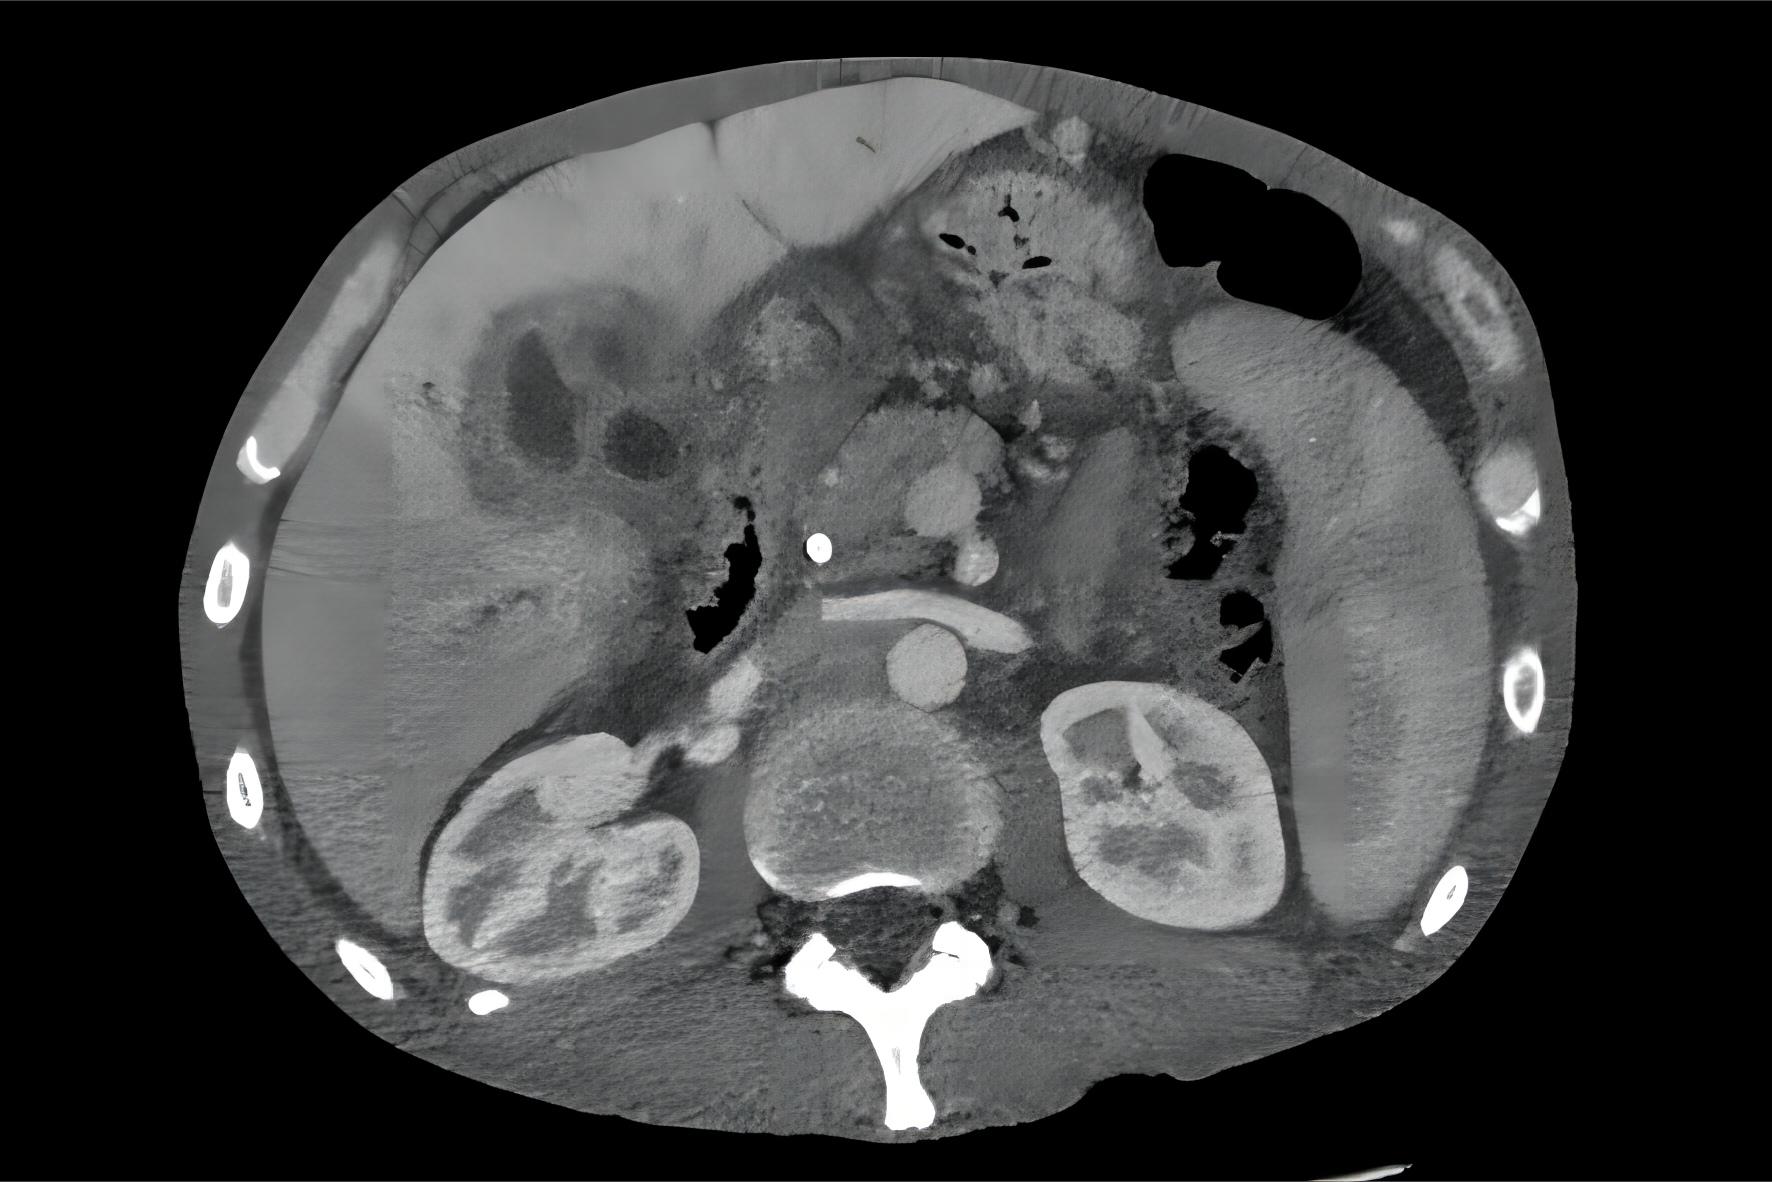

Fig.2 Liver cancer. (From English Wikipedia: By Samir, https://commons.wikimedia.org/wiki/File:CT_cholangioca.jpg) Distributed under CC BY-SA 3.0, from Wiki, without modification. Liver Cancer

The high expression of BAZ2A in liver cancer cells has certain influence on the migration and invasion ability of liver cancer cells. The migration and invasion ability of liver cancer cells can be reduced by inhibiting the expression of BAZ2A, to achieve the effect of tumor inhibition.